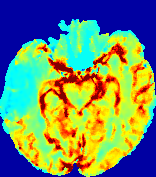

LesionRefer to captionRefer to captionRefer to captionRefer to captionRefer to captionRefer to caption𝐕rgbsubscript𝐕𝑟𝑔𝑏{\bf{V}}_{rgb}Refer to captionRefer to captionRefer to captionRefer to captionRefer to captionRefer to caption𝐕2subscriptnorm𝐕2{\|\bf{V}}\|_{2}Refer to captionRefer to captionRefer to captionRefer to captionRefer to captionRefer to captionRefer to caption3.53.53.52.82.82.82.12.12.11.41.41.40.70.70.70.00.00.0(mm/s)𝑚𝑚𝑠(mm/s)D𝐷DRefer to captionRefer to captionRefer to captionRefer to captionRefer to captionRefer to captionRefer to caption0.0200.0200.0200.0160.0160.0160.0120.0120.0120.0080.0080.0080.0040.0040.0040.0000.0000.000(mm2/s)𝑚superscript𝑚2𝑠(mm^{2}/s)Slice #1Slice #2Slice #3Slice #4Slice #5Slice #6

Figure 3: PIANO feature maps for one stroke patient, where the lesion is located in the left hemisphere. Top row: segmented stroke lesion region (white) on different slices, obtained from ISLES 2017. The corresponding slices for the PIANO feature maps are shown in the following rows.

For a better insight into an estimated velocity field 𝐕𝐕{\bf{V}} and diffusion field 𝐃𝐃{\bf{D}}, we compute the following maps: (1) 𝐕rgbsubscript𝐕𝑟𝑔𝑏{\bf{V}}_{rgb}: Color-coded orientation map of 𝐕=(Vx,Vy,Vz)T𝐕superscriptsuperscript𝑉𝑥superscript𝑉𝑦superscript𝑉𝑧𝑇{\bf{V}}=(V^{x},V^{y},V^{z})^{T}, obtained by normalizing 𝐕𝐕{\bf{V}} to unit length and mapping its 3 components to red, green, blue respectively; (2) 𝐕2subscriptnorm𝐕2\|{\bf{V}}\|_{2}: 222 norm of 𝐕𝐕{\bf{V}}; (3) D𝐷D: scalar field in Eq. 5.

Fig. 3 and Fig. 4 show the PIANO feature maps estimated from two ISLES 2017 patients: all are highly consistent with the lesion in both cases. Details of the blood flow trajectories are revealed in 𝐕rgbsubscript𝐕𝑟𝑔𝑏{\bf{V}}_{rgb} by the ridged patterns and the sharp changes of colors in the unaffected (right) hemisphere, while the flat patterns appearing within the lesion provide little directional information about the velocity and indicate low velocity magnitudes. Velocity magnitudes are more directly visualized via 𝐕2subscriptnorm𝐕2\|{\bf{V}}\|_{2}, from which one can easily locate the lesion where 𝐕2subscriptnorm𝐕2\|{\bf{V}}\|_{2} is low. D𝐷D also indicates lower diffusion values in the lesion, though with less contrast potentially due to the fact that it captures the accumulated effect of CA diffusion at the voxel-level.